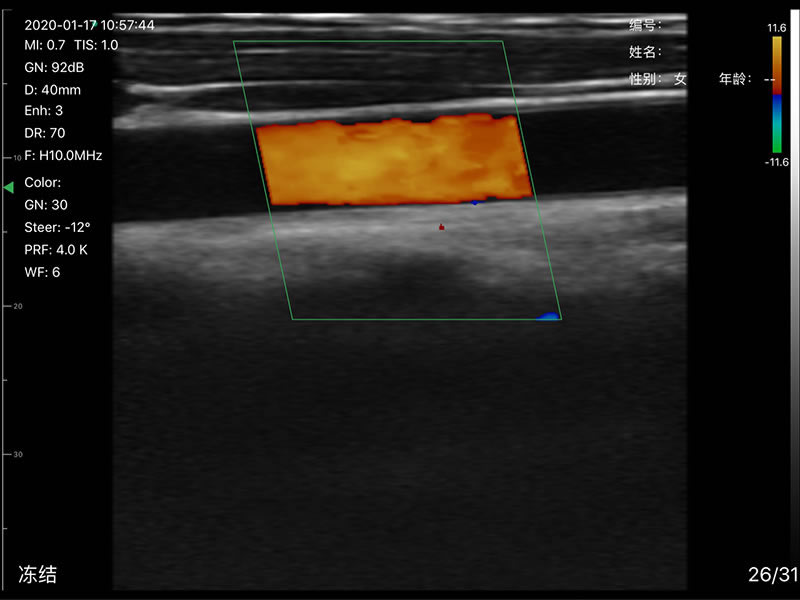

• 探头频率:相控阵2.2/3.6MHz,线阵7.5/10 MHz

• 扫描声头:同时具备微凸、线阵两个声头,并可通过按键快速切换

• 扫描深度:相控阵20-240mm,线阵 20-100mm,可调

• 扫描角度和宽度:相控阵80mm,线阵25mm

• 显示模式:B、B/M、Color、PW、PDI